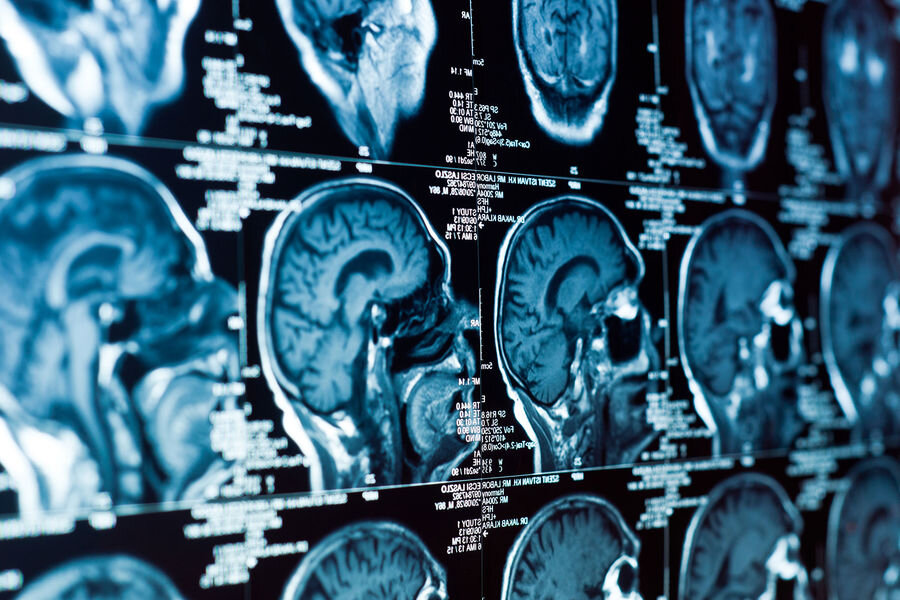

Leybnits adına Primatlar Tədqiqatları İnstitutunun alimləri müəyyən ediblər ki, ARHGAP11A geni inkişaf edən insan beynində unikallığı ilə seçilən hüceyrə quruluşunun formalaşmasında əsas rol oynayır.

Alimlər izah ediblər ki, insan beyni heyvanların beynindən geniş qabıq sahəsi, mürəkkəb quruluşu və hüceyrələrin böyük müxtəlifliyi ilə fərqlənir. Bu xüsusiyyətlər hələ inkişaf dövründə, staminal hüceyrələrin sinir və dəstək hüceyrələrinə çevrildiyi ventrikulyar zonada formalaşır. Lazımi qatlara bölünmək və ora köçmək üçün hüceyrələr daim onların formasını və böyümə istiqamətini müəyyən edən daxili “çərçivə” - sitoskeleti yenidən qurur.

Tədqiqatçılar müəyyən ediblər ki, ARHGAP11A bu prosesləri idarə edir. Gen normal işlədikdə staminal hüceyrələr düzgün istiqamətlənir, lazımi yerdə qalır və lazım olan sürətlə bölünür. Gen olmadığı zaman hüceyrələr toxumanı vaxtından əvvəl tərk edir və neyronlara çevrilir. Bu isə staminal hüceyrə ehtiyatının sürətlə tükənməsinə və beynin yetkinləşməsi və sabitliyi üçün vacib olan dəstək hüceyrələrinin çatışmazlığına gətirib çıxarır.